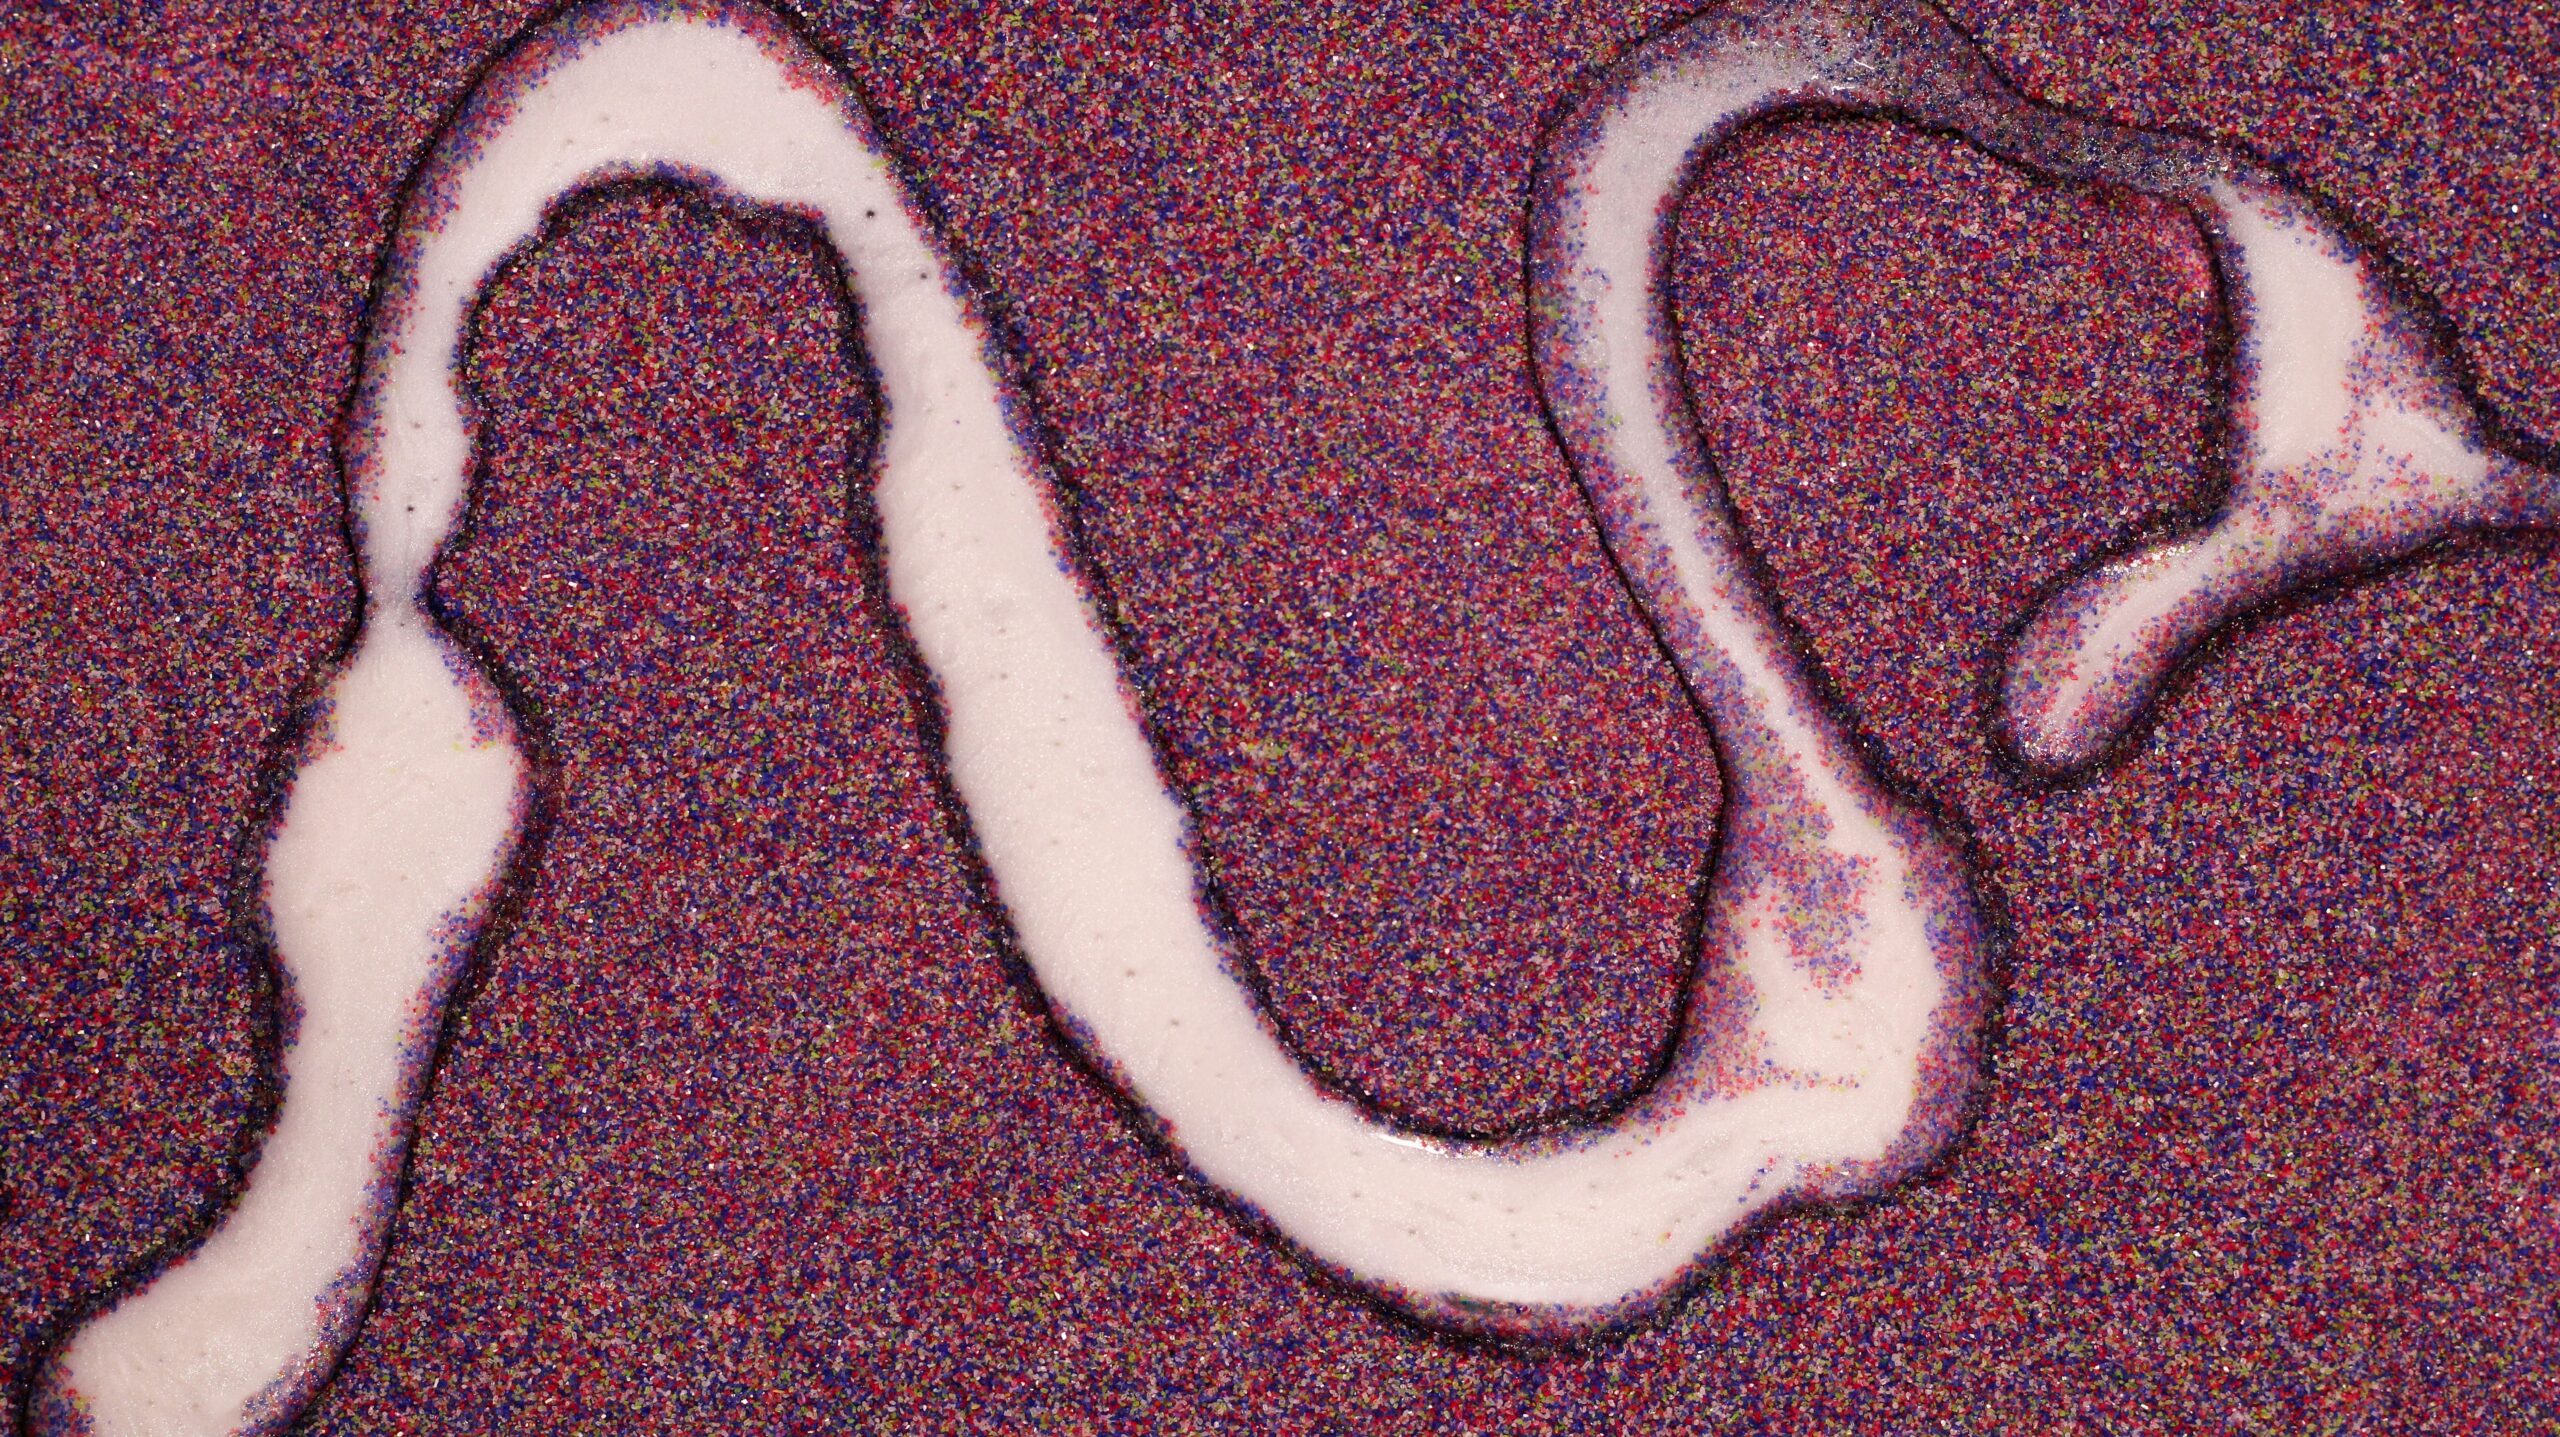

La GnRH, ou hormone de libération des gonadotrophines hypophysaires, désigne une neurohormone sécrétée par l’hypothalamus, une petite glande située dans le cerveau.

Elle agit sur la glande pituitaire qui elle-même contrôle la libération des hormones FSH (hormone folliculostimulante) et LH (hormone lutéinisante). La FSH et la LH contrôlent quant à elles le cycle hormonal (par la production des œstrogènes et de la progestérone).

Ainsi, le jeûne intermittent a un impact sur l’axe hypothalamo-hypophyso-gonadique (HPG). L’axe hypothalamo-hypophyso-gonadique est constitué de trois glandes (hypothalamus et hypophyse dans le cerveau et gonades/ovaires). Il contrôle le cycle menstruel par le biais de la production des différentes hormones féminines. Cela signifie que le jeûne va avoir un impact sur le fonctionnement du cycle menstruel de la femme par le biais d’une action sur les hormones reproductrices féminines. Explications.

Le jeûne intermittent induit un stress dans le corps des personnes qui le pratique par le biais de la chute de la glycémie et de son impact sur l’insuline (la science n’a pas encore expliqué les choses en détail mais cela pourrait avoir un lien avec la kisspeptine, une molécule utilisée par les neurones pour communiquer entre eux). Ce stress est considéré par le corps comme un danger pour sa survie (comme d’ailleurs un sommeil insuffisant, un excès d’effort physique ou une charge mentale et émotionnelle trop forte). Comme la reproduction et la survie doivent être coordonnées et équilibrées, l’axe HPG est capable de moduler (et d’être modulé par) la signalisation des hormones de stress, notamment la corticostérone, provenant de l’axe hypothalamo-hypophyso-surrénalien (HPA). Les surrénales sont de petites glandes situées au-dessus des reins qui gèrent notamment les hormones du stress.